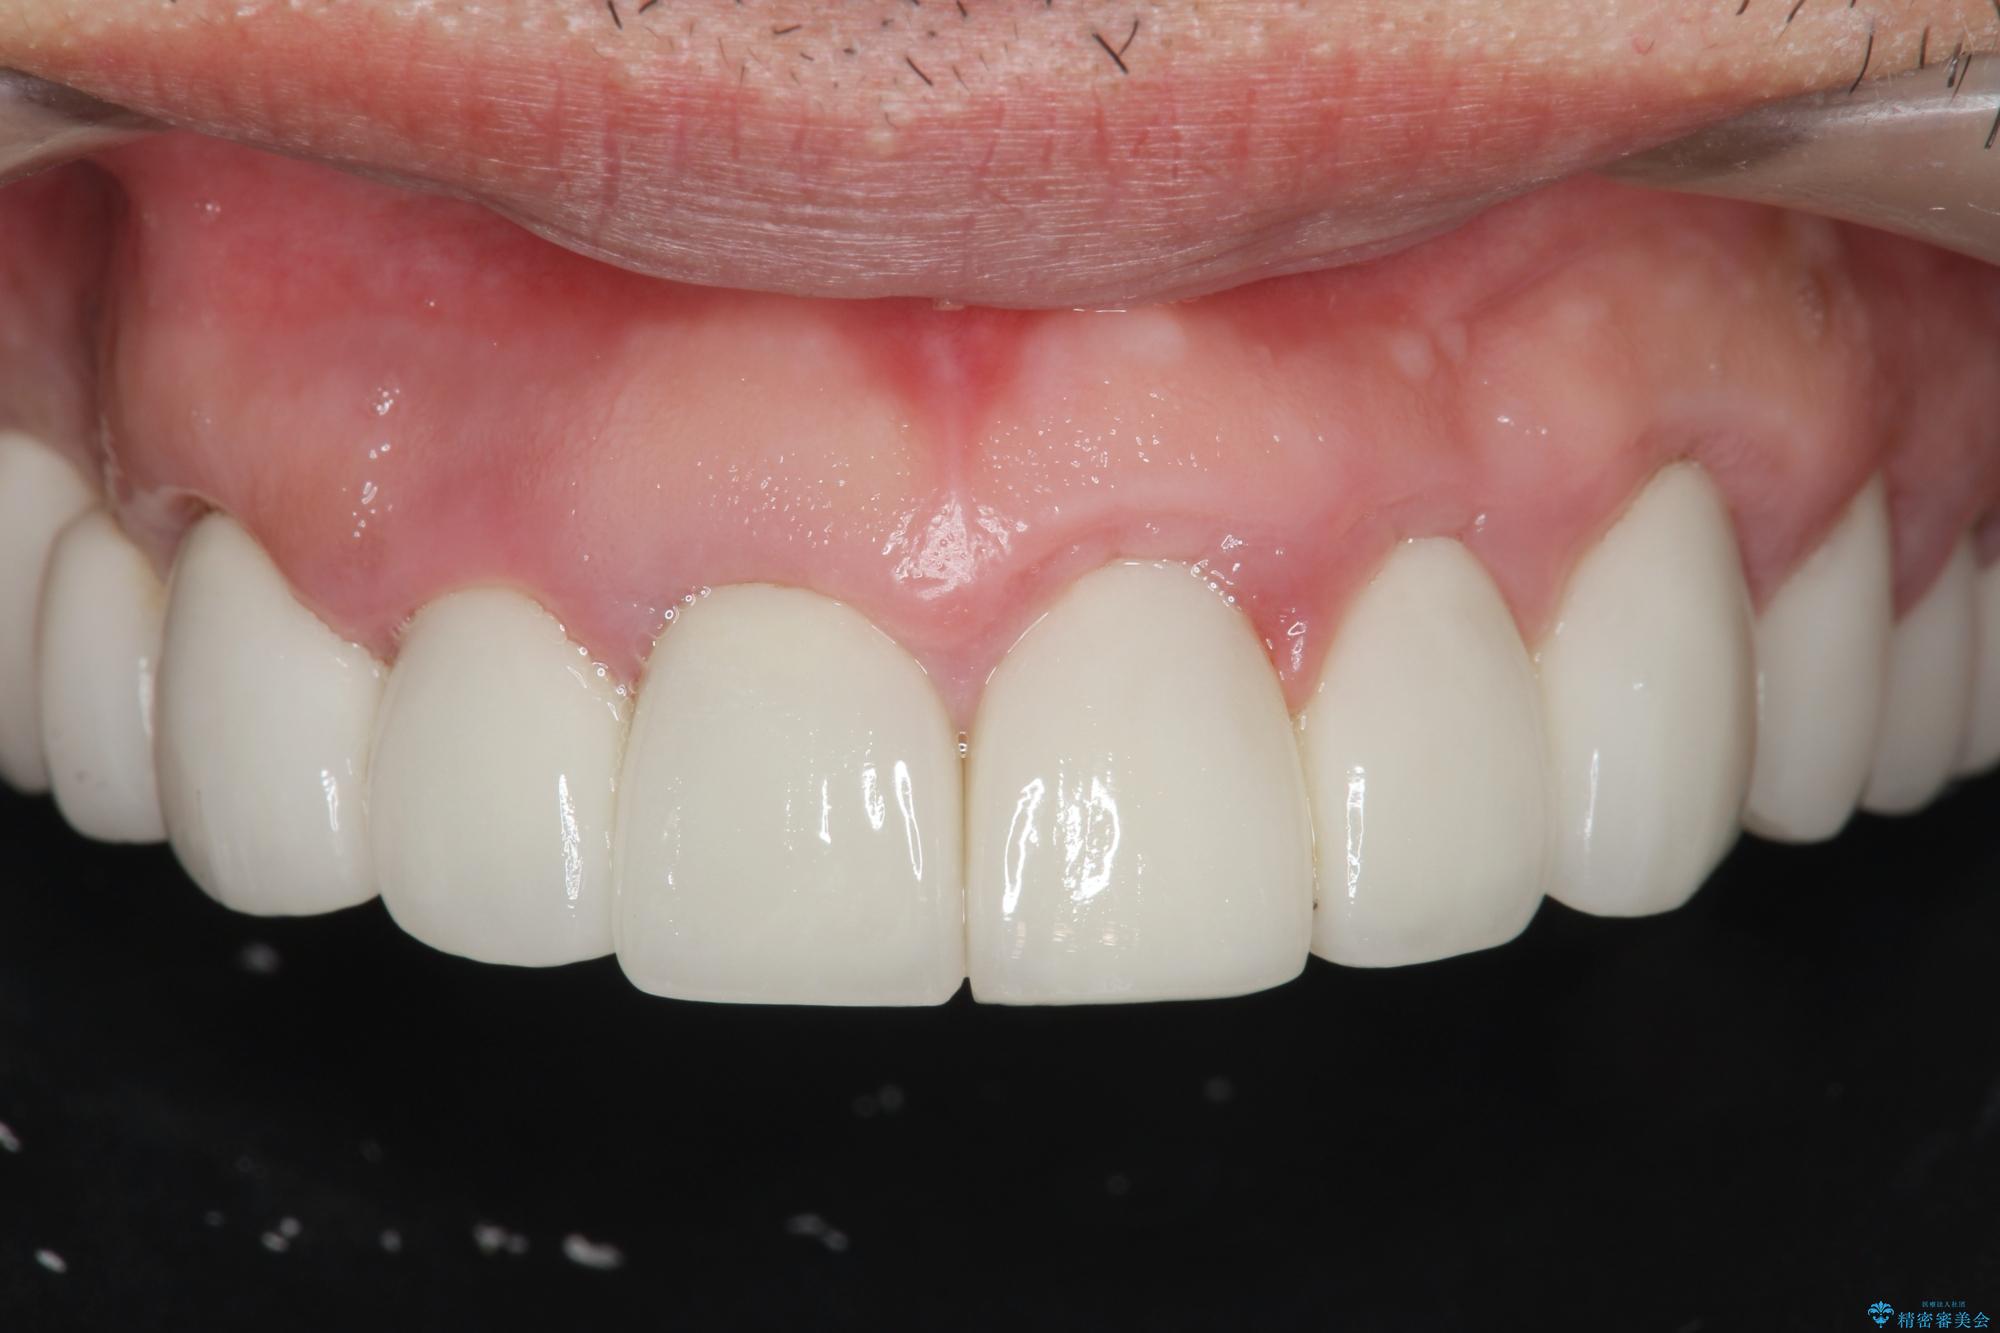

- 「セラミック治療を他院で受けたが、それ以来歯ぐきが腫れ違和感がある、改善してほしい。」と歯ぐきの状態改善を希望され来院されました。

セラミッククラウンを除去し仮歯を装着し、歯周外科手術を行い歯ぐきの状態を改善したのち、適合の良いセラミッククラウンを再作製をする治療計画としました。

- 90.2万円(ジルコニアクラウン×6・仮歯×6 ・歯周外科手術)費用は治療当時の料金となります

見た目の良いクラウンが装着されていても、歯ぐきの状態が悪ければ違和感や歯ぐきの腫れ、臭いの元となっていることが多く見られます。